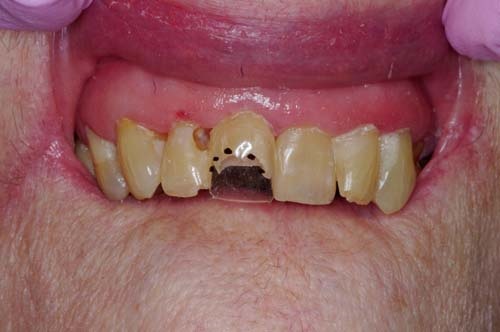

After removal of the caries (Fig. 3, p. 27) I fitted a generic strip crown and marked the junction to her facial enamel on the crown form (Fig. 4, p. 27). This allowed me to know exactly where to place the darker conventional composite as a facial veneer (Fig. 5). This veneer would not interfere with the benefits of the flowable bioactive composite for both the placement and the sustainability of the restoration.

Fig. 3: After caries removal. Note the lack of restorations at age 94, a fine example of a life with good diet and excellent oral care. However, as the patient declines, so does her personal hygiene and, together with xerostomia, rampant caries becomes a major challenge.